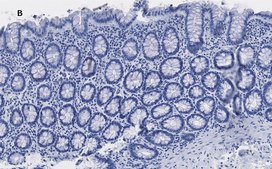

Immunohistochemistry (Paraffin) Analysis: A 1:100 dilution from a representative lot detected trimethyl-Histone H3 (Lys4) in human colon and human breast cancer tissue sections.